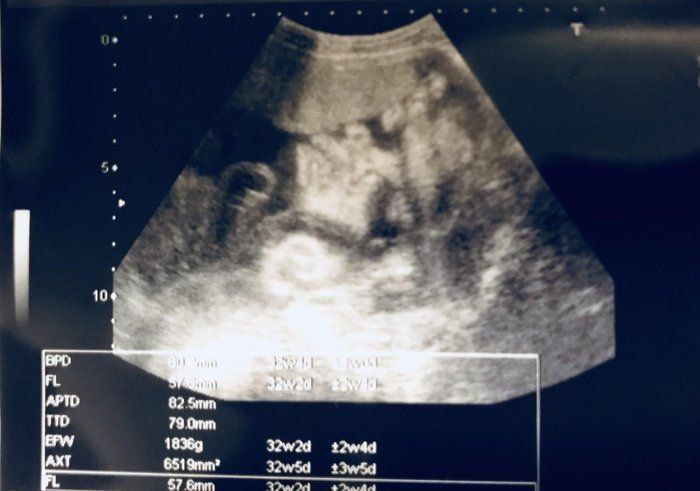

クリコさんの妊娠30週目のエコー写真

赤ちゃんの大きさは標準の真ん中あたり。胎盤の位置や羊水の量も正常、母子ともに問題はありませんでした。

ムチムチの赤ちゃんの顔がアップになった4D写真。出産まで3カ月をきり、改めて「出産準備をしなければ」と、焦り始めました。